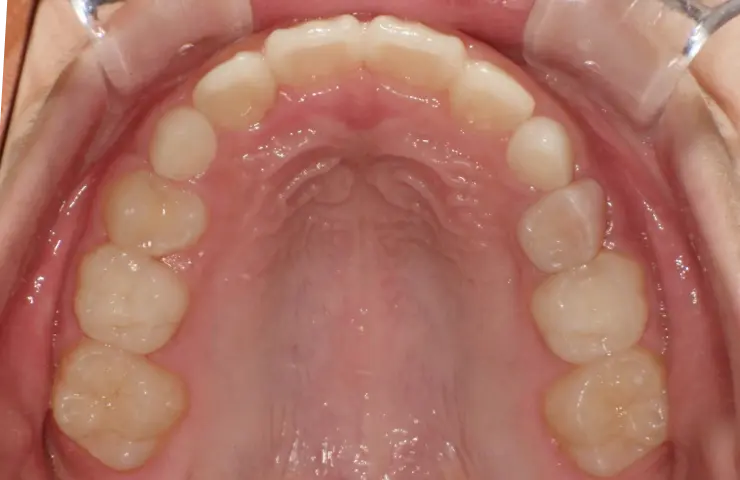

治療症例